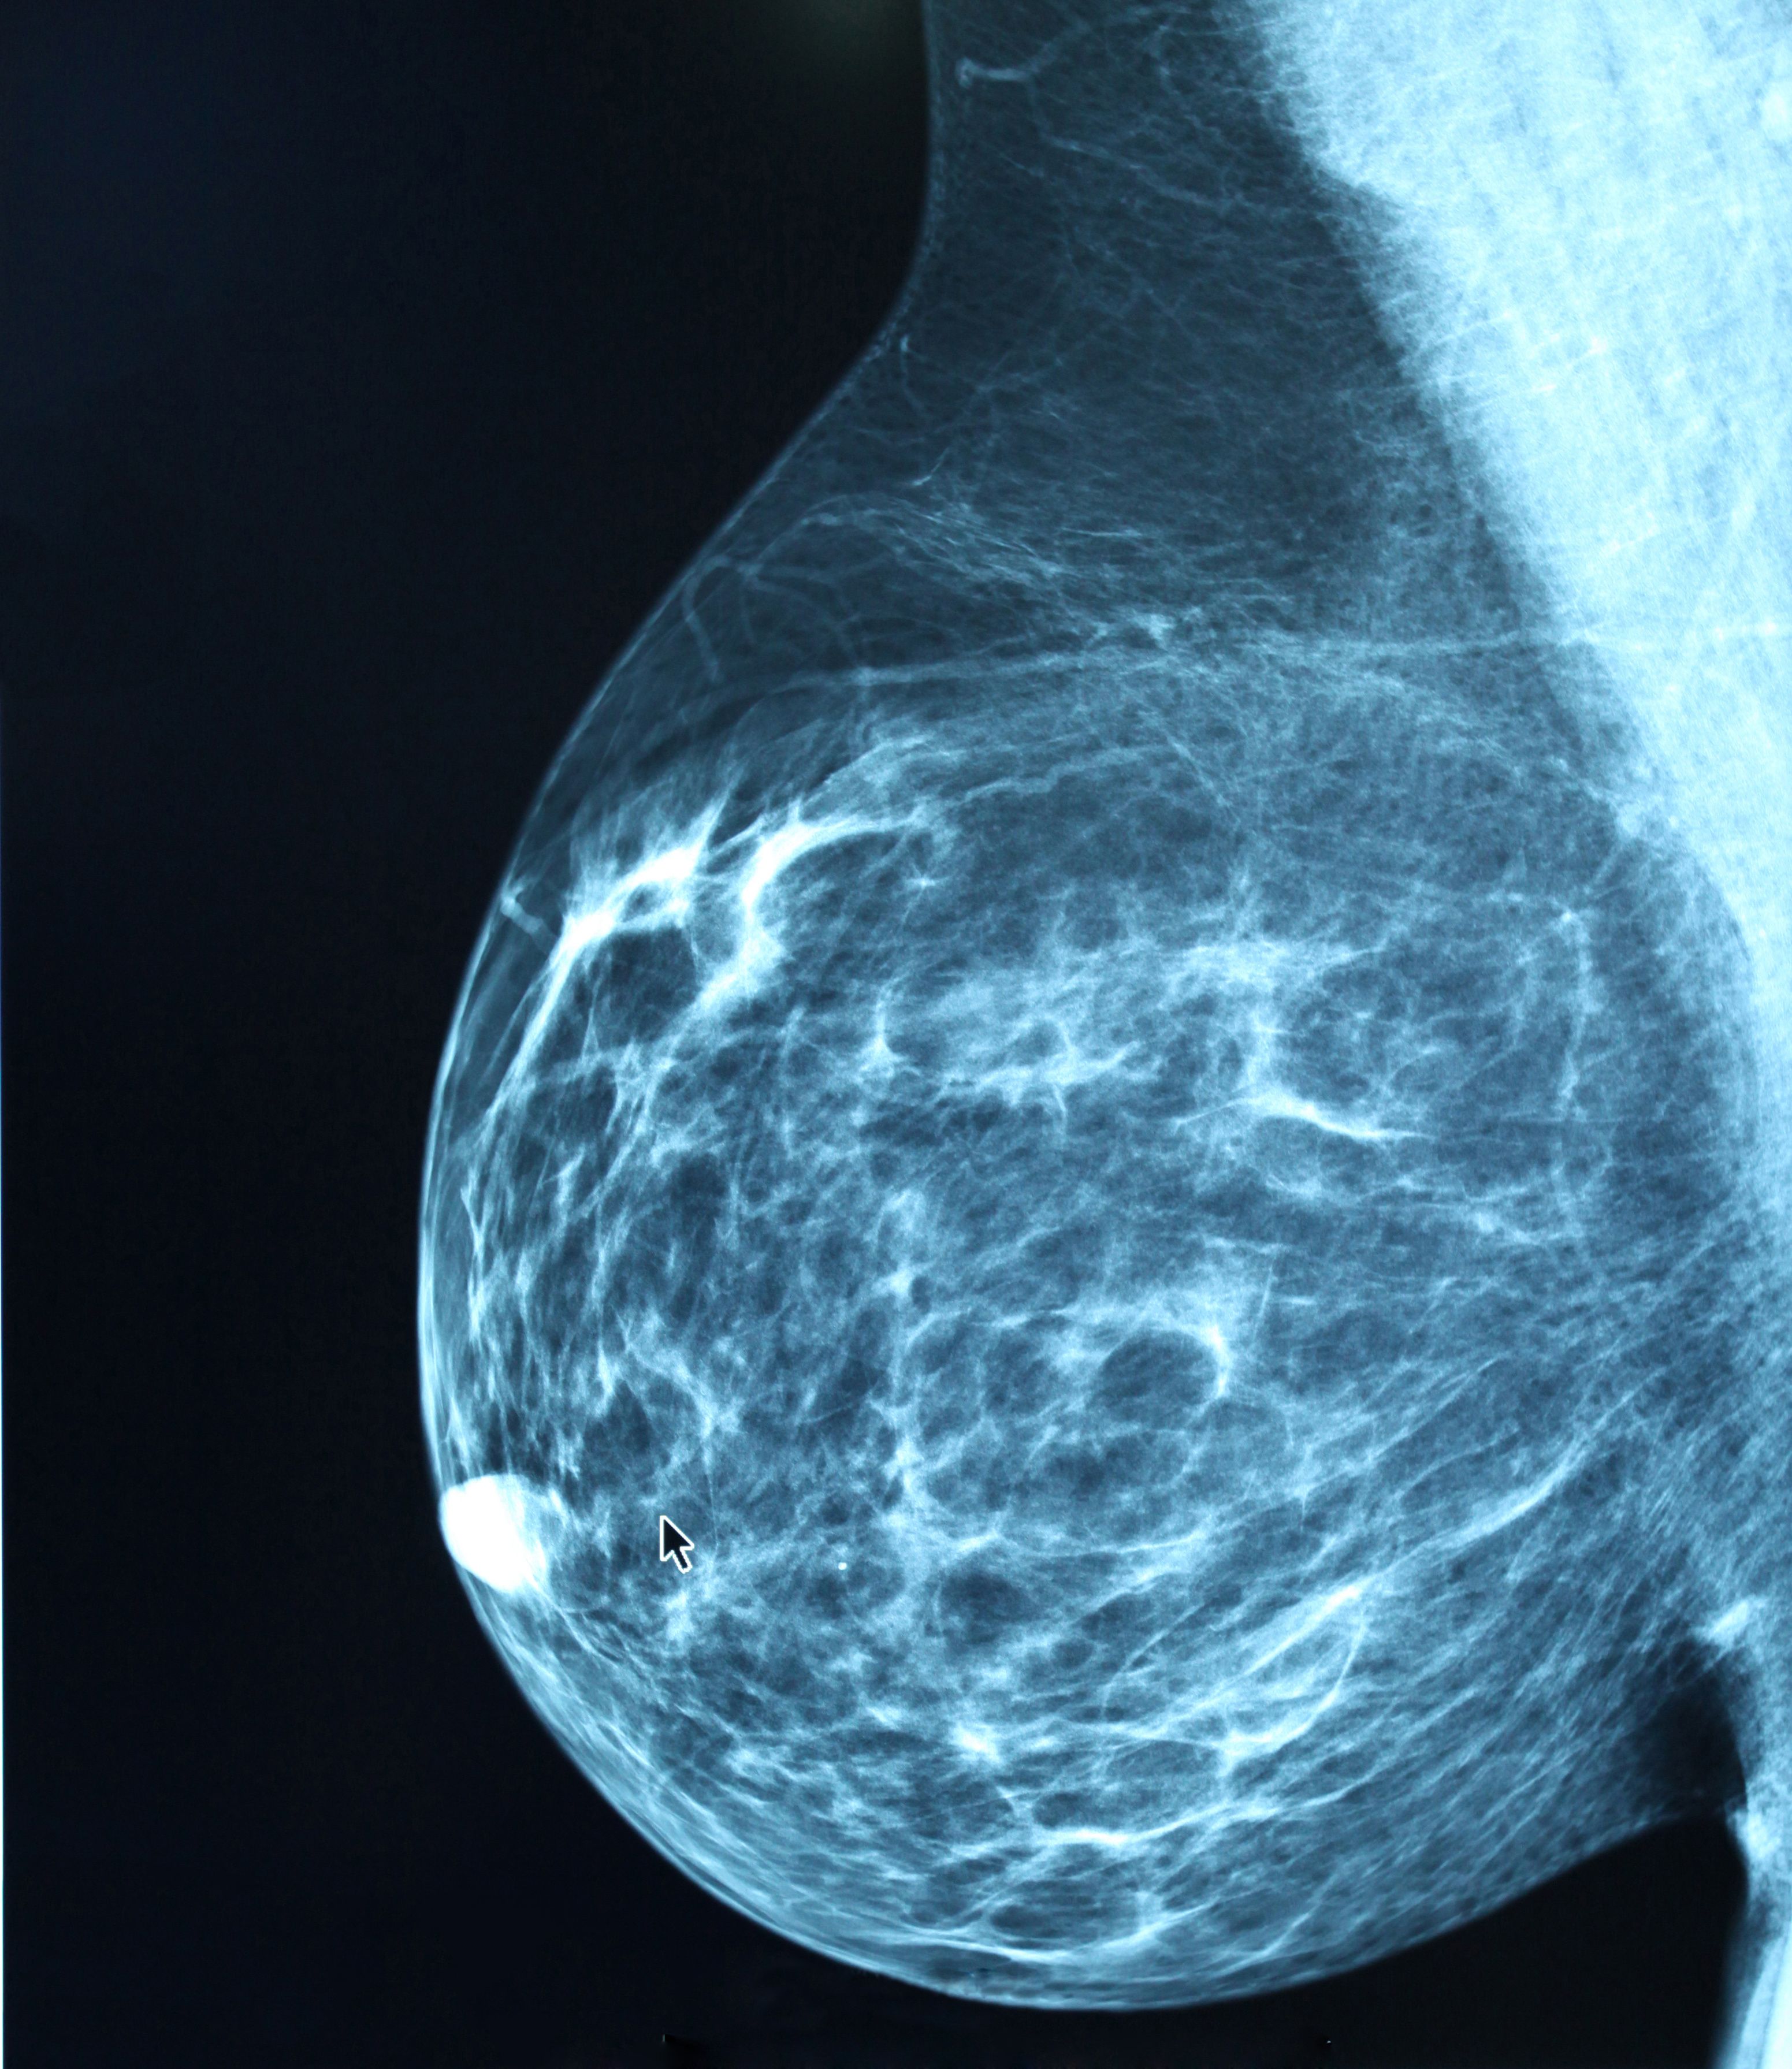

Advances in Imaging Technology

Mammography remains the gold standard for breast cancer screening but has well-established limitations. Use of advanced techniques purport improved cancer detection over full-field digital (2D) mammography alone. Appropriate use of advanced imaging technologies for screening may help maximize the overall benefit-to-harm ratio of screening average-risk women. We review these advanced imaging technologies here.47

Advances in Mammographic Imaging

Many of the pivotal RCTs informing guideline recommendations were completed with film-screen mammography. However, digital mammography is now widely used across the United States. The Digital Mammographic Imaging Screening Trial found no significant difference between film-screen and digital mammography in imaging sensitivity across more than 49,000 women in the United States and Canada.48 However, digital mammography had significant benefit over film-screen mammography when used in pre- and perimenopausal women, women younger than 50 years,49 and women with dense breasts.48